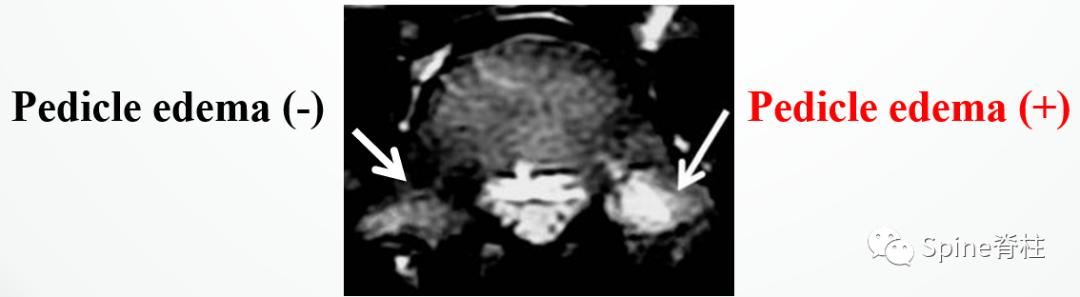

有研究发现磁共振上 椎弓根出现T2高信号改变是青少年和儿童峡部裂的早期诊断征象 。同时, 存在椎弓根高信号改变也是保守治疗后能达到骨性愈合的良好预测指标 (也就是说存在T2椎弓根右高信号改变的峡部裂患者,其峡部裂经保守治疗愈合的可能性大) 。

右上图为椎弓根高信号改变(+),右下图为(-)

左侧为椎弓根水肿阳性,右侧为椎弓根水肿阴性,有研究发现峡部裂伴随着椎弓根水肿,支具固定愈合率更高

Sairyo教授研究发现磁共振上 椎弓根出现T2高信号改变是青少年和儿童峡部裂的早期诊断征象 。同时,存在椎弓根高信号改变也是保守治疗后能达到骨性愈合的良好预测指标(也就是说存在T2椎弓根右高信号改变的峡部裂患者,其峡部裂经保守治疗愈合的可能性大)。

图:右上图为椎弓根高信号改变(+),右下图为(-)